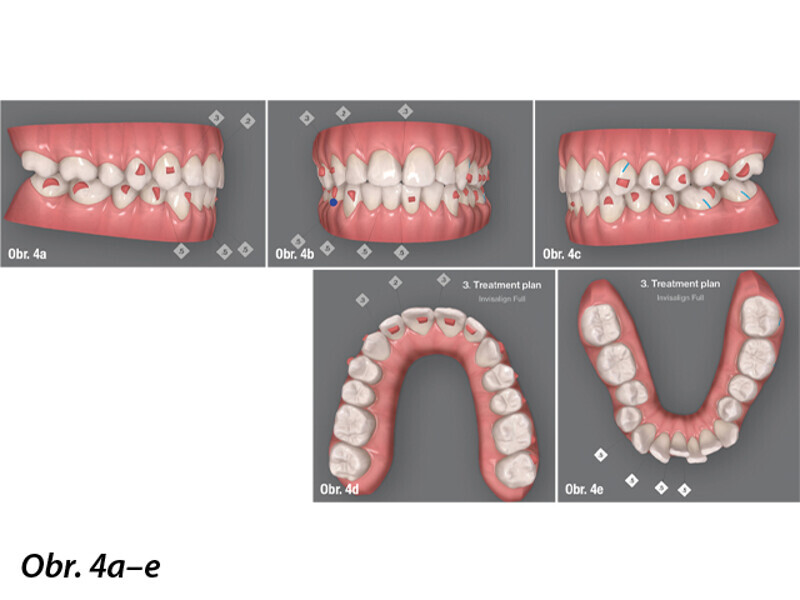

Ortodontická léčba komplexních případů malokluze pomocí průhledných alignerů